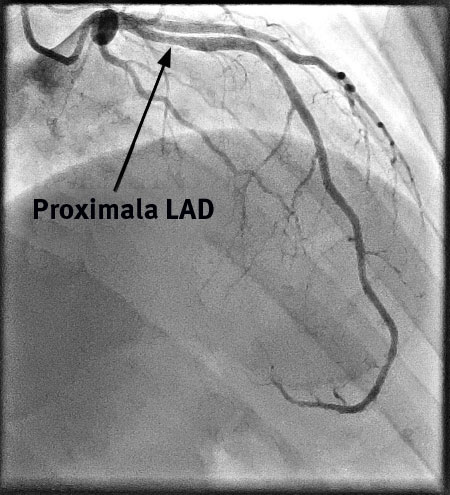

Fallbeskrivning Frisk kvinna insjuknade under träning efter en enda dos